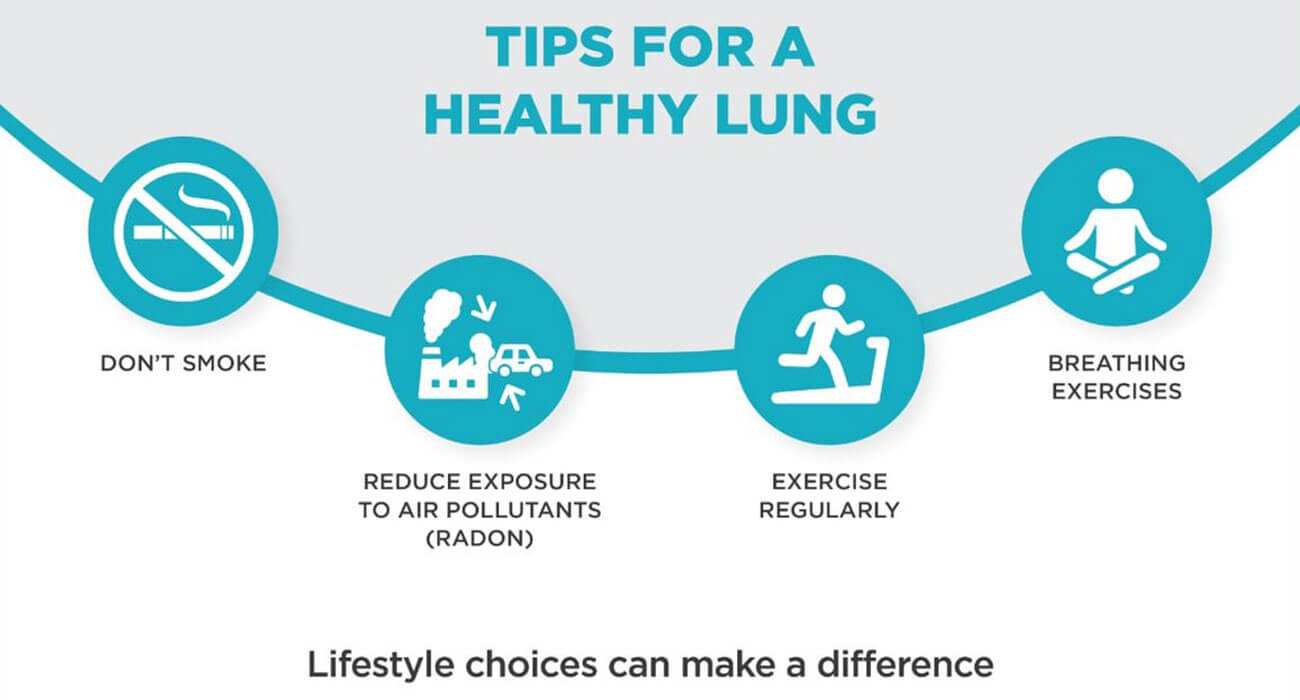

Why is it important to keep your lungs healthy? Lungs are an integral part of our body system. The proper functioning of the lungs is essential for breathing, supplying oxygen to the whole body and removing carbon dioxide from your body. Change in environment, dust, dirt, pollution and genetic factors are responsible for lung damage and may cause many respiratory…

An overview As per a report by WHO, Indian cities have seen an unexpected exponential increase in pollution especially post Diwali leading to a dip in oxygen levels. This has led to a humongous upsurge in the cases of various respiratory issues. Pollution level is soaring high, people are suffering from issues like breathlessness, allergies, cough, cold which targets our…

Citing the reports, approximately 90% of lung cancer cases are linked with cigarette smoking. Dr. Satya Ranjan Sahu, a renowned pulmonologist practicing in South Delhi says, “Smoking cigarettes directly impacts the lungs of humans along with their key functioning. The changes that are thus created are both reversible and irreversible, depending on the situation that might easily turn fatal for…